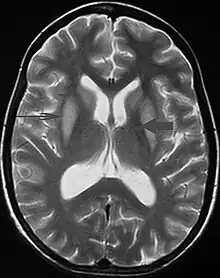

Axial fat-saturated T2-weighted image showing hyperintensity in the pons with sparing of the peripheral fibers, the patient was an alcoholic admitted with a serum Na of 101 treated with hypertonic saline, he was left with quadriparesis, dysarthria, and altered mental status

It can be diagnosed clinically in the appropriate context, but may be difficult to confirm radiologically using conventional imaging techniques. Changes are more prominent on MRI than on CT, but often take days or weeks after acute symptom onset to develop. Imaging by MRI typically demonstrates areas of hyperintensity on T2-weighted images.[29]